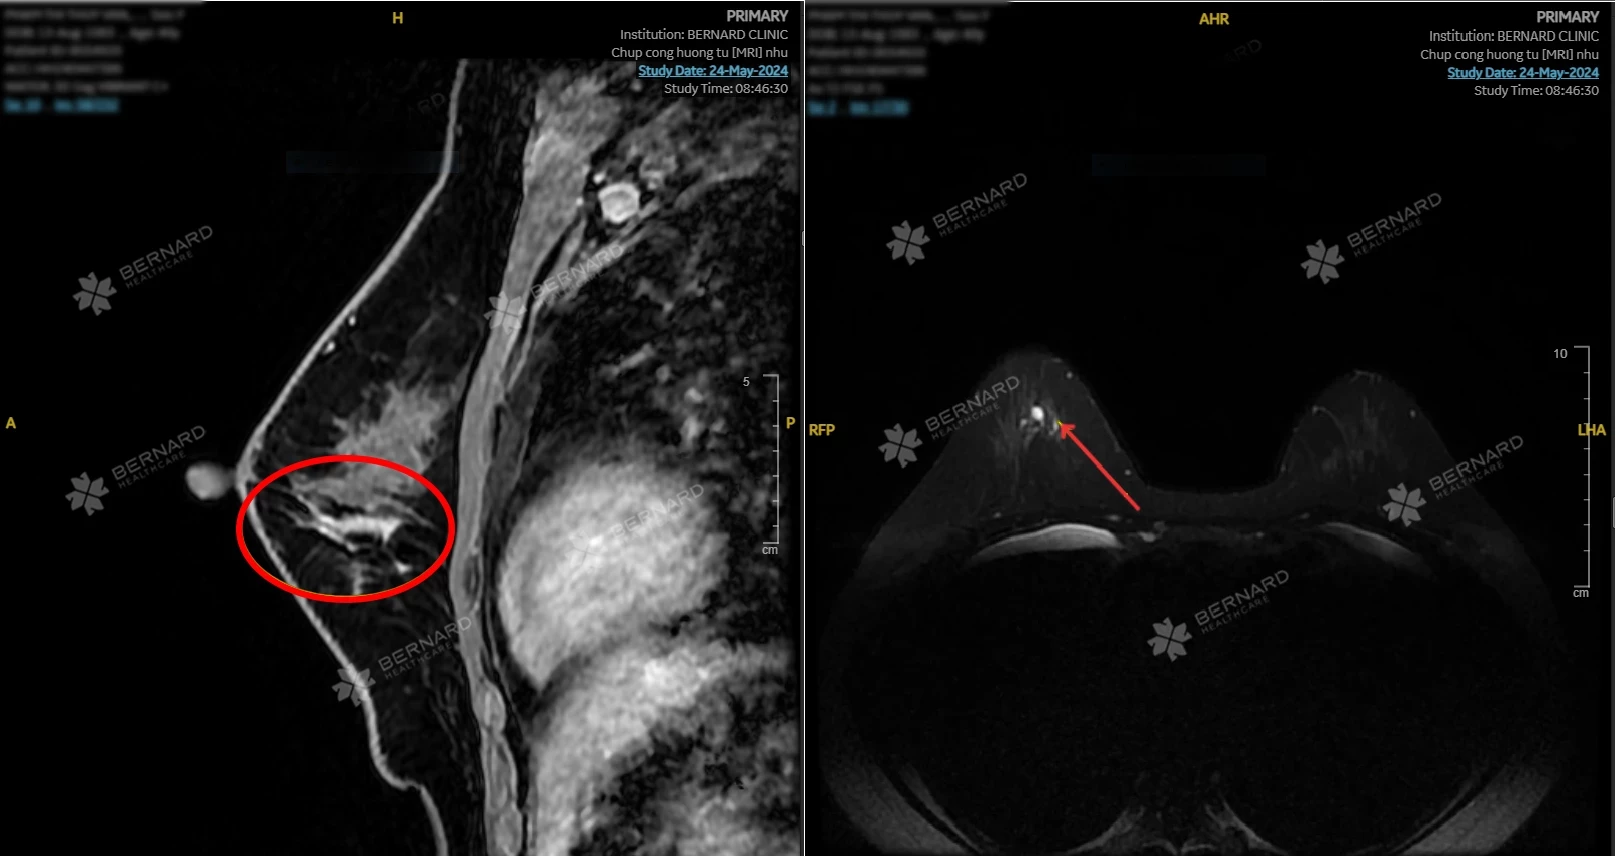

- Chụp cộng hưởng từ (MRI) tuyến vú động học có tiêm tương phản

Giúp phát hiện sớm ung thư vú; Bệnh lành tính do đặt túi như bao xơ co thắt, rò rỉ túi, BIA-ALCL (lymphoma liên quan túi ngực); Tình trạng viêm - tự miễn liên quan đến túi ngực nhám (theo cảnh báo của FDA Hoa Kỳ).